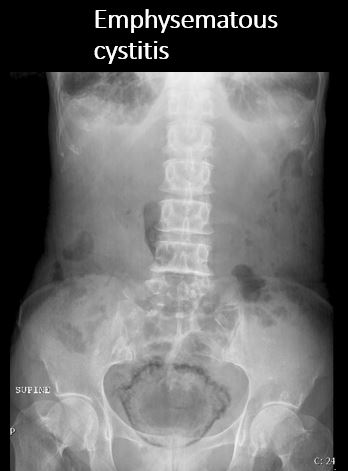

There is air in the urinary bladder wall or in the lumen. |

No | NA |